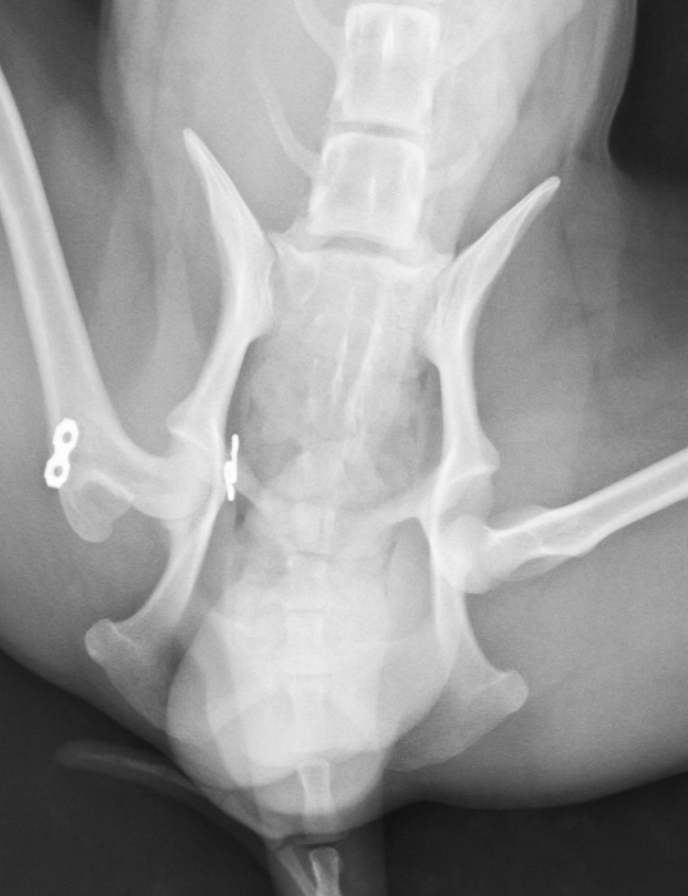

この子は遊んでいたら右後肢を挙上するとのことで来院され、レントゲン画像検査にて右股関節脱臼が確認されました。直ぐに手術を行い脱臼を整復しました。手術にはトグルピン法を行いました。

術後順調に回復していましたが、1ヶ月後には反対足を挙上するとのことで来院され、反対側の脱臼が確認されました。

そのため、すぐに反対足も同様の手術を行うことで脱臼を整復しました。

その後の経過は順調で、すぐに歩行開始し(術後2日目には普通に歩行可能でした)、その後再脱臼もせず、普段どおり生活しているとのことでした。